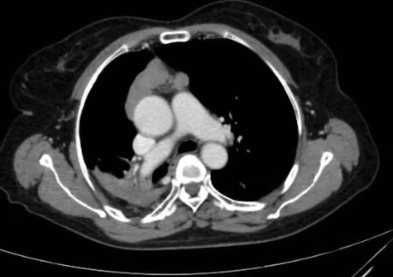

患者为72岁女性,因“体检发现前纵膈占位性病变1周”入院,胸部CT提示前纵膈一大小约10*6*5cm病灶。检查发现患者瘤体较大,有周围脏器血管受侵,且肺功能差,在科室主任李贵宣、副主任赵云统筹下,科室与麻醉科团队密切协作,经过充分术前准备后,李建主治医生在西南医科大学附属医院胸外科徐涛教授(对口支援)的指导下,为患者成功实施了单孔剑突下入路纵膈肿瘤切除术。术后患者恢复良好,切口愈合快,术后第3天拔管办理出院。